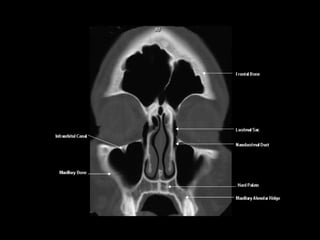

Radiographers use medical imaging equipment like X-rays and MRIs to produce images of patients' internal structures and organs. They are responsible for positioning patients, operating scanning machines, and ensuring quality images. Radiographers must have strong attention to detail, excellent communication skills, and the ability to work well under pressure to accurately capture anatomical features and diagnose any abnormalities.